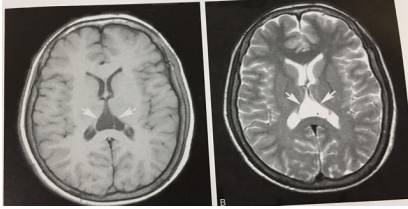

3、血管周围间隙扩大,VR

T1WI显示右侧基底节外下部类圆形低信号灶,T2WI呈高信号。

4、第五脑室(透明隔间腔)

T1WI及T2WI显示双侧侧脑室体部间槽状脑脊液信号影,边界清晰。

5、第六脑室

T1WI及T2WI显示透明隔后方不规则囊状灶,与脑脊液信号一致,边界清楚。

6、双侧侧脑室发育不对称

T1WI及T2WI显示双侧侧脑室发育不对称,右侧侧脑室发育相对较大,左侧侧脑室发育正常,脑组织信号正常。